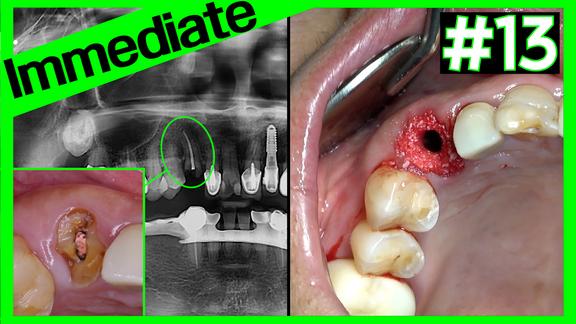

#13 immediate implant placement (KSⅢ) with dual zone graf...

Online Surgery

Vistas 16